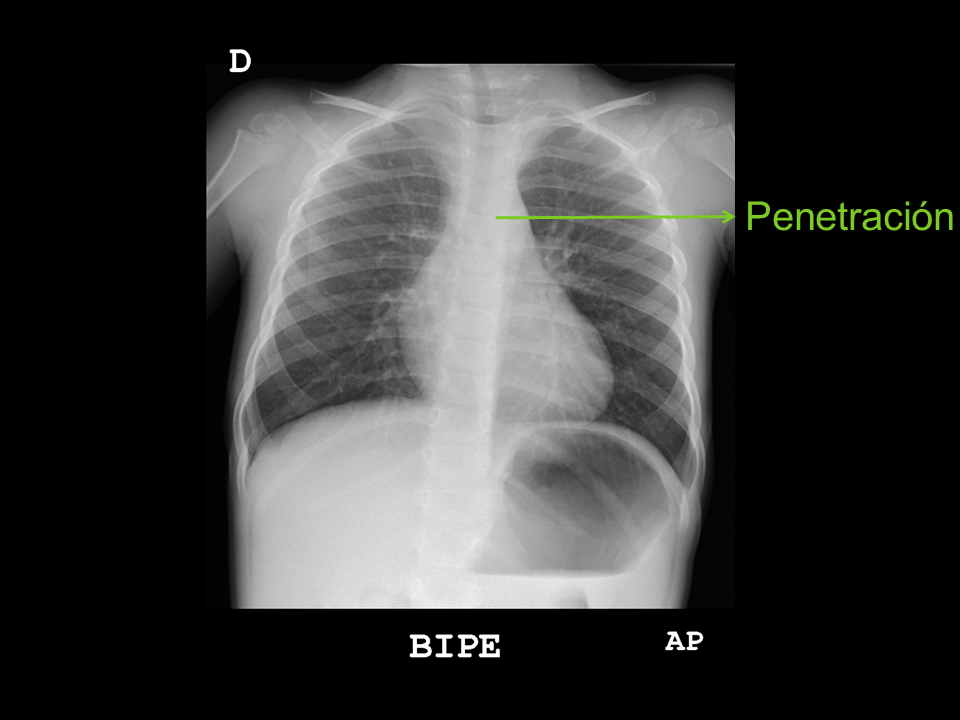

• Penetración: debemos visualizar los espacios intervertebrales a través de la silueta cardiaca.